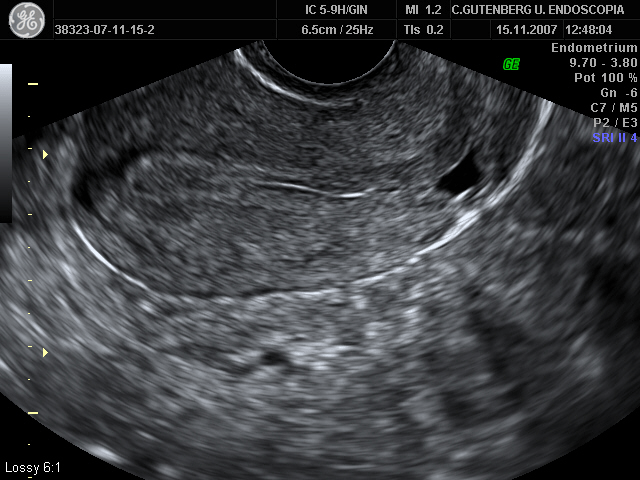

When performing a pelvic ultrasound in patients with history of cesarean section, it is frequent to find a hypoecogenic area, generally triangular with the vertex directed towards the bladder of different sizes, at the level of the previous caesarean section scar. This ultrasound image, defined as an “Isthmocele”. It is a uterine wall sac-like structure located in the lower uterine wall, just in the area of the scar of a previous cesarean section.

The diagnosis of isthmocele is based on clinical signs and complementary tests such as ultrasound, hysterosonography and/or hysteroscopy. The ultrasound shows the presence of an hypoecogenic area, generally of triangular shape, located at the isthmic level with the vertex of it directed towards the bladder (3). This isthmocele is echographically more evident if ultrasound is performed during the postmenstrual phase, since blood accumulation facilitates the visualization as an ecogenic area. The measures that are usually carried out in this ecogenic area, are the ones to measure their area, following the formula (base x height / 2), classifying the

istmoceles according to the result in 3 degrees, grade 1 when the area is less than 15 mm², Grade 2 between 16 and 24 mm² and grade 3 when it is greater than 25 mm².